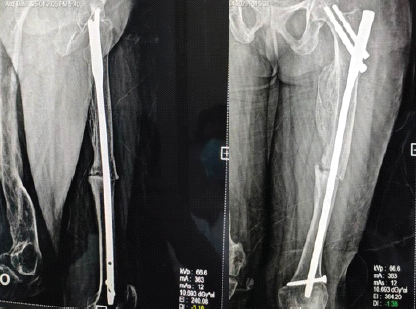

Patient pre-anesthetic evaluation workup was done and posted for surgery. The patient was placed supine on a fracture table, after standard painting and draping, and slight traction was applied. Moreover, closed reduction of the fracture was attempted and achieved under C-arm guidance. A small lateral incision was made proximal to the greater trochanter. An entry point was made at the tip of the greater trochanter under image guidance, and a guidewire was passed through the proximal femur into the shaft. Reaming was done over the guidewire sequentially. A long proximal femoral nail (PFN) (length: 28 cm, diameter: 9 mm) was inserted over the guidewire. Fracture alignment was confirmed under C-arm. 8 mm and 6 mm proximal locking screws were inserted through the jig. Distal locking was done using the freehand technique under C-Arm. Final fluoroscopy confirmed satisfactory fracture reduction, implant position, and screw placement. The wound was irrigated with saline, and hemostasis was ensured. Wound closure was done in layers. A sterile dressing was applied. The post-operative patient was allowed toe-touch with a Zimmer walking frame. Clinical and radiographic follow-up showed no displacement and consolidation after 8 weeks, and hence, full weight-bearing was started as tolerated. The patient was followed up after 5 months, and her physical status was almost comparable to the pre-operative level without any complications (Fig. 3, 4, 5, 6).

Figure 3: Immediate post-operative X-rays.

Figure 4: Partial-weight bearing X-rays after 2 weeks.